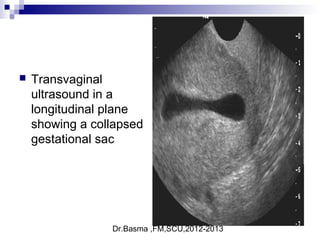

 Transvaginal

ultrasound in a

longitudinal plane

showing a collapsed

gestational sac

Signs suggestive of abnormal embryonic developmentSigns suggestive of abnormal embryonic development

 a collapsed gestational sac